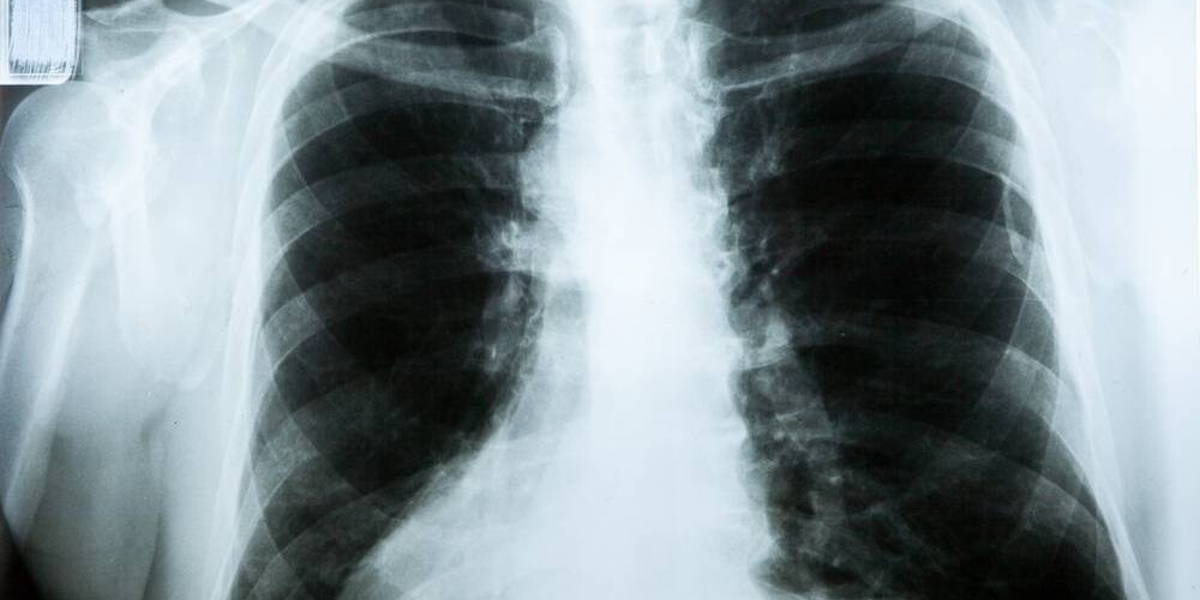

Het beoordelen van een röntgenfoto van de longen door een of meerdere radiologen is een van de snellere manieren om de diagnose COVID-19 te stellen. Het inzetten van kunstmatige intelligentie kan de radiologen daarbij helpen, zo blijkt uit onderzoek dat door het Jeroen Bosch Ziekenhuis (JBZ), Radboudumc en Bernhoven uitgevoerd is.

Een door middel van deep learning en kunstmatige intelligentie (AI) getrainde computer kan bij het beoordelen van longfoto's even goed voorspellen of iemand infiltratieve longafwijkingen heeft als een radioloog. De afgelopen periode zijn meer AI-methoden ontwikkeld en onderzocht die mogelijk kunnen bijdragen aan het sneller herkennen van COVID-19 of de impact die de ziekte heeft op longen. Het AI-systeem van het JBZ wordt nu verder doorontwikkeld.

Het onderzoek van JBZ, Radboudumc en Bernhoven maakt gebruik van het deep learning-systeem CAD4COVID-XRay. Tijdens het 'trainen' van de AI-methode is het systeem 'gevoed' met röntgenfoto's van gezonde longen uit andere ziekenhuizen. Vervolgens zijn 454 longfoto's van het JBZ beoordeeld door zowel het AI-systeem als de radiologen. In alle gevallen kwamen zowel het AI-systeem als de radiologen tot dezelfde beoordeling of diagnose; of er al dan niet een (COVID-19) longontsteking op de foto zichtbaar is.